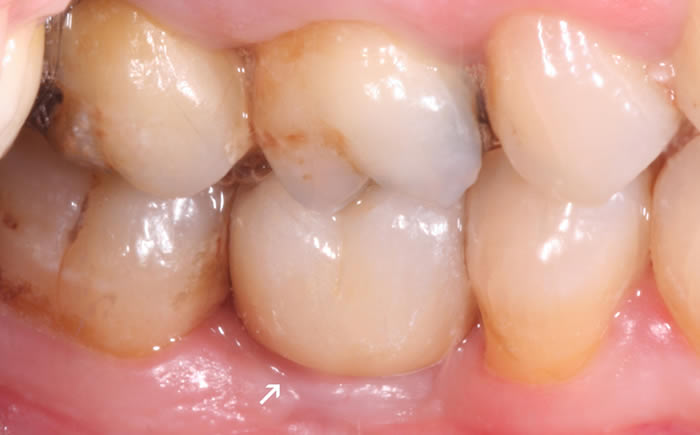

More back teeth replaced by dental implants

Case Three (2 images)

Case Four (4 images)

Case Five (4 images)

Case Six (8 images)

Case Seven (4 images)